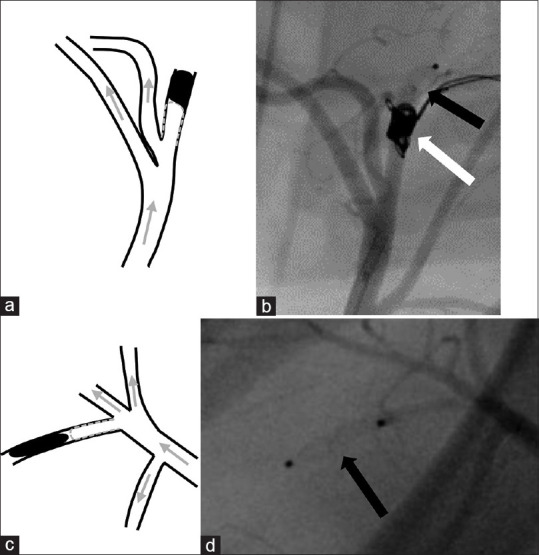

Materials and methods: For aneurysm creation in external carotid and subclavian arteries, Amplatzer vascular plugs were used as occlusion devices, leaving simple stumps that serve as surrogate aneurysms. If necessary and anatomically possible, additional embolic materials, such as coils and liquid embolic agents were used.

Results: We created 42 aneurysms. Aneurysm creation was possible without complications in all cases. There was no spontaneous thrombosis of fabricated aneurysms. Complete perfusion arrest behind the fabricated aneurysm was challenging but achieved in 45% of cases. We were not able to identify significant factors that have an impact on the persisting perfusion of fabricated aneurysms on final imaging, particularly not the presence of side branches in the aneurysm lumen (P = 0.734) or volumes of the fabricated aneurysms (P = 0.620). Albeit not significant, the use of additional occlusive measures (coils, liquid embolic agents) and antithrombotic drugs (ASA, heparin and tirofiban) may be factors for persisting perfusion: Perfusion arrest behind the fabricated aneurysm was twice as high in animals treated with ASA and heparin compared to animals treated with ASA, heparin, and tirofiban (48% vs. 22%; P = 0.149).